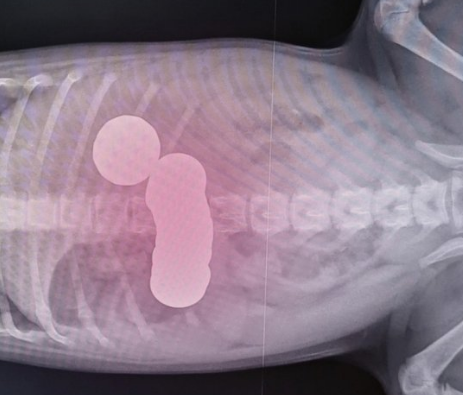

- 위장관이 막혀있는 경우도 있어요

- ex) 복숭아씨, 자두씨를 먹어서 막힌 경우

- 이런 씨앗은 엑스레이 검사에서 보일 수도 안 보일 수도 있어요

- X-ray 검사

- 위장관이 막혀있는지

- 다른 질환 진단 (X-ray로 진단되지 않는 경우도 있음)